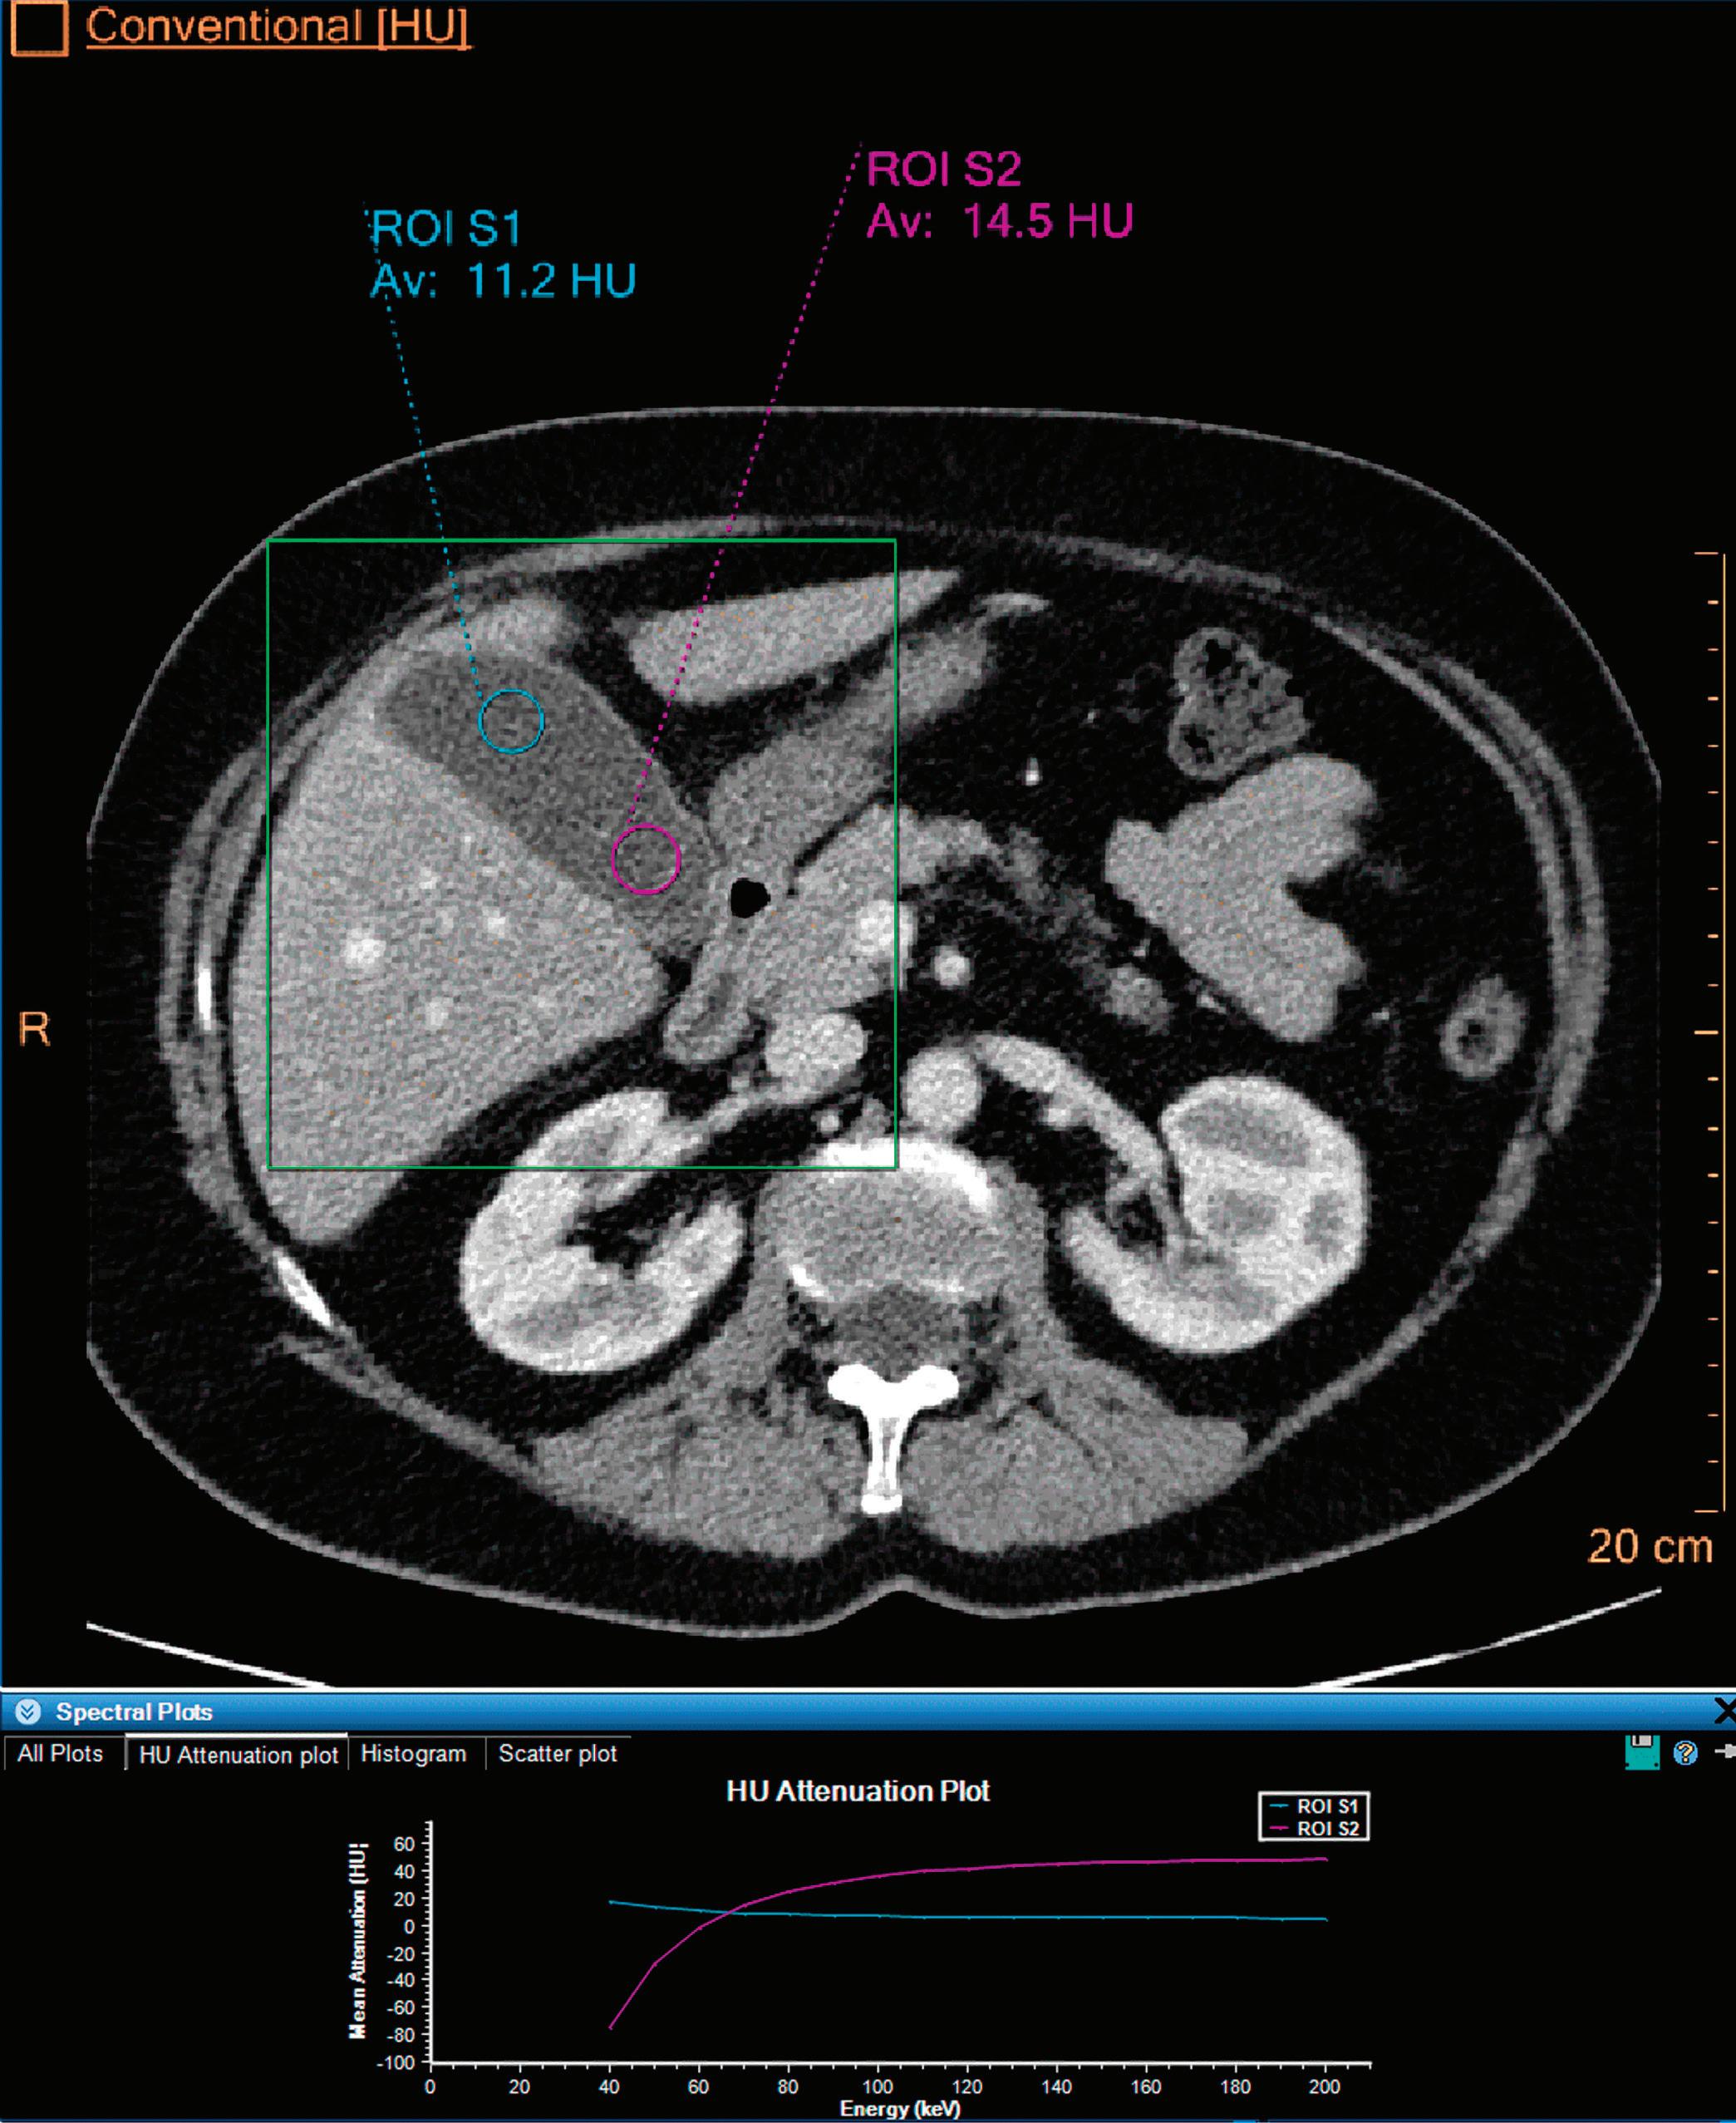

3 (Left)

Patient presented to the emergency department with abdominal pain. The conventional CT does not reveal any abnormality in the gallbladder. In the middle row, spectral attenuation curves reveal two different materials: a first region of interest (purple) with a CT number that is increasing with energy, typical of a low Z effective element (below the Z effective value of water), and a second region of interest (blue) with a CT number that is decreasing with the energy, typical of a Z effective above water. The differentiation between the two materials cannot be performed based on the conventional CT because the two attenuation curves cross each other around 70 keV (where the attenuation is equivalent to the conventional CT). The lower row displays spectral results in the Magic Glass, from left to right: 40 keV image, 200 keV image, iodine density image, and Z effective map. A gallstone is clearly revealed on the 40 keV image and with an inverted contrast on the 200 keV image. The iodine density shows a perfusion defect of the gallbladder wall due to the compression with the gallstone (white arrow), and the Z effective helps us to determine the gallstone composition with a Z effective below 6.5 typical of a cholesterolic composition.